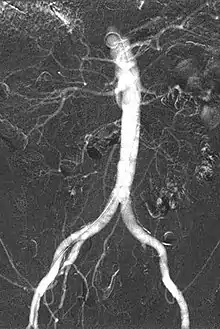

CO2 Angiogram showing Abdominal Aorta, visceral arteries and iliac arteries

Carbon dioxide angiography is a diagnostic radiographic technique in which a carbon dioxide (CO2) based contrast medium is used - unlike traditional angiography where the contrast medium normally used is iodine based – to see and study the body vessels.[1] Since CO2 is a non-radio-opaque contrast medium, angiographic procedures need to be performed in digital subtraction angiography (DSA).

The CO2 does not mix with blood. At atmospheric pressure CO2 is in gaseous form and, when it comes out from the catheter, it forms a train of bubbles which displaces blood, causing a transient ischemia, in relation to the bloodstream (systolic pressure). When added together by DSA “stacking” software,[5] the result is a composite diagnostic image of the frames.